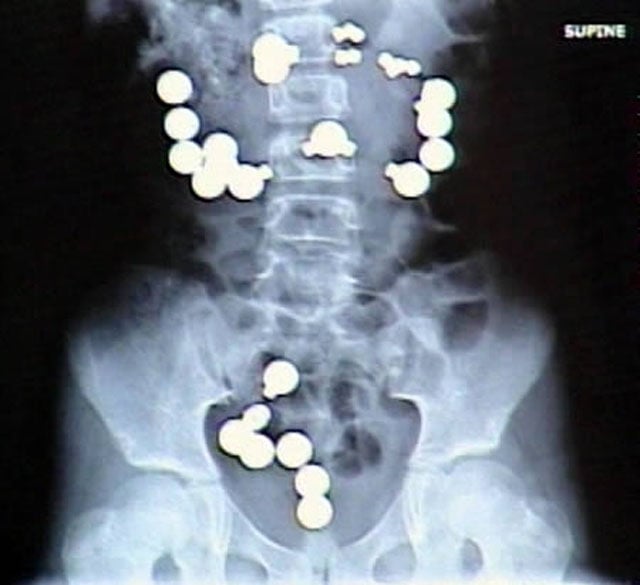

8-year-old Haley Lents of Indiana swallowed 10 magnets and 20 steel balls from a Magnetix toy set. The magnets and balls attracted one another within her digestive tract, ripping a total of eight holes in her intestines and forcing her parents to rush her to the hospital for emergency surgery. Lents later told reporters that the magnets and steel balls "looked like candy"